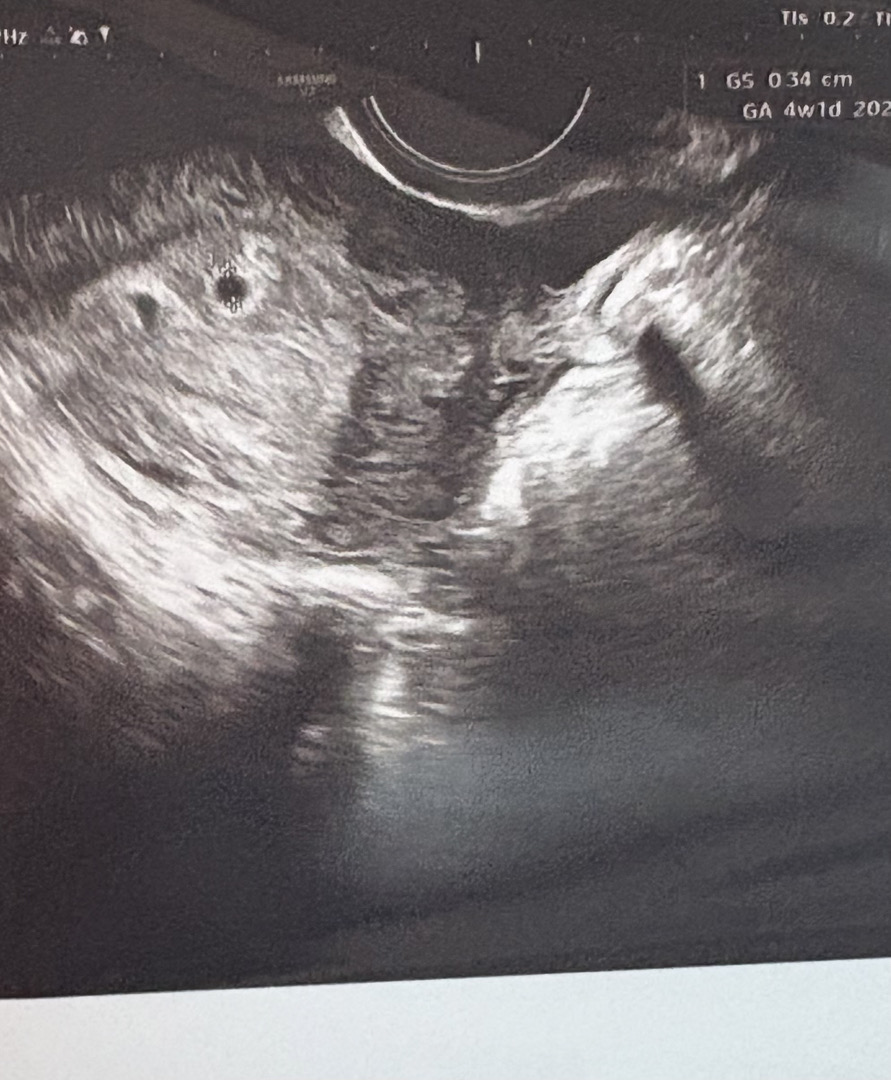

막생기준 4주6일 병원에선 4주1일이래요 0.34cm 잘 크겠죠? 병원에서 볼 땐 몰랐는데 계속 보다보니 아기집 왼쪽으로 비슷하게 생긴게 있는거 같은데.. 아기집일까요?.. 피고임이려나요?.. 아기집이였으면 병원에서 얘기해줬겠죠? 자연이고 가족력도 없어서 아닐꺼같긴한데.. 토요일에 병원가는데 궁금해죽겠어요 ㅠㅠㅠㅠ 쓰리라인만 주구장창 하고있네요.. 쓰리라인 1번 선이 아주 약간 더 진한데 토요일에 가면 심장소리 들릴지 ㅜㅜ